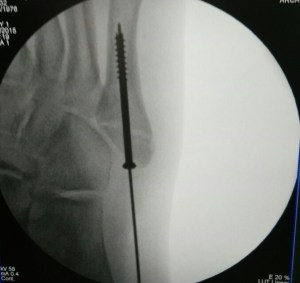

Percutaneous cannulated screw fixation of this displaced avulsion fracture of the 5th metatarsal base was performed.

This procedure is done via a small incision and guided by x-rays fluroscopy.